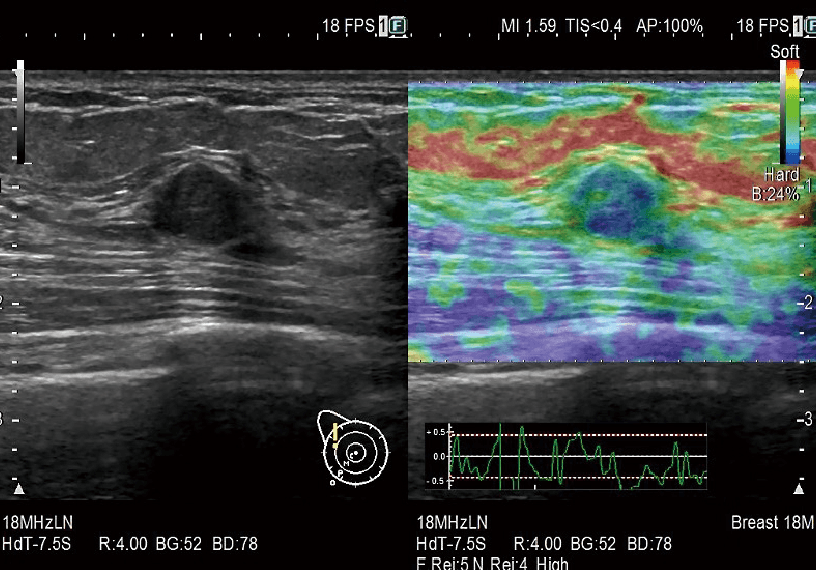

RTE assesses tissue strain in real time and displays the tissue stiffness as a color map. Its application has been validated in a wide variety of clinical fields including the breast, and it is possible to calculate an estimated elasticity value for liver fibrosis staging.